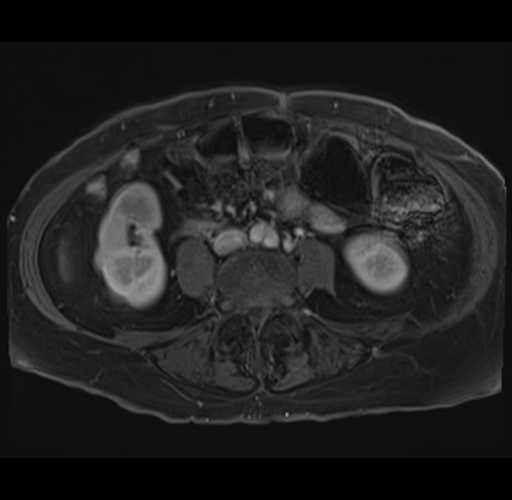

MRI T1